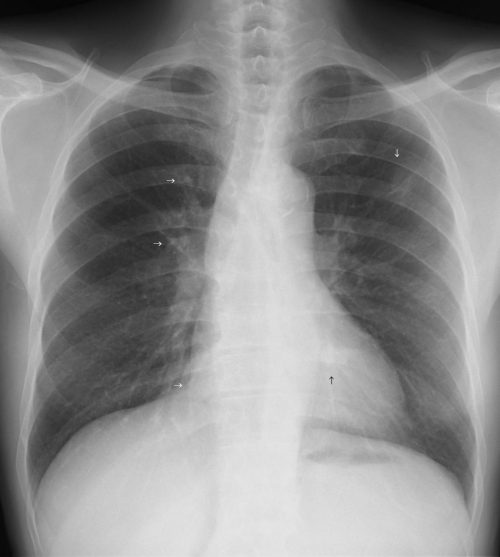

A.正常像(成人) 読影のチェックポイント さらに詳細に読影 最低限の読影項目 以上を参考に実際に上の正常像を読影

①左右対称、適切な黒化度・コントラストで撮影されている。

②胸郭、横隔膜に異常みとめず正しく吸気位である。

③鎖骨、気管、縦隔、心陰影、脊椎(胸椎・頸椎)、大動脈弓、続く胸部大動脈は異常をみとめず。

④肺野は左右とも透過度は良好、肺門ならびに肺動脈、気管支の走行は正常。

⑤右上葉と中葉の葉間の葉間間裂の線状影がみられるが、肺の異常影は(孤立性陰影を含む)みとめられない。

⑥心陰影は右辺縁・左辺縁ともに正常、心拡大もみられない。

[評価] 撮影条件は良好、異常陰影等みられず正常のレントゲン像。